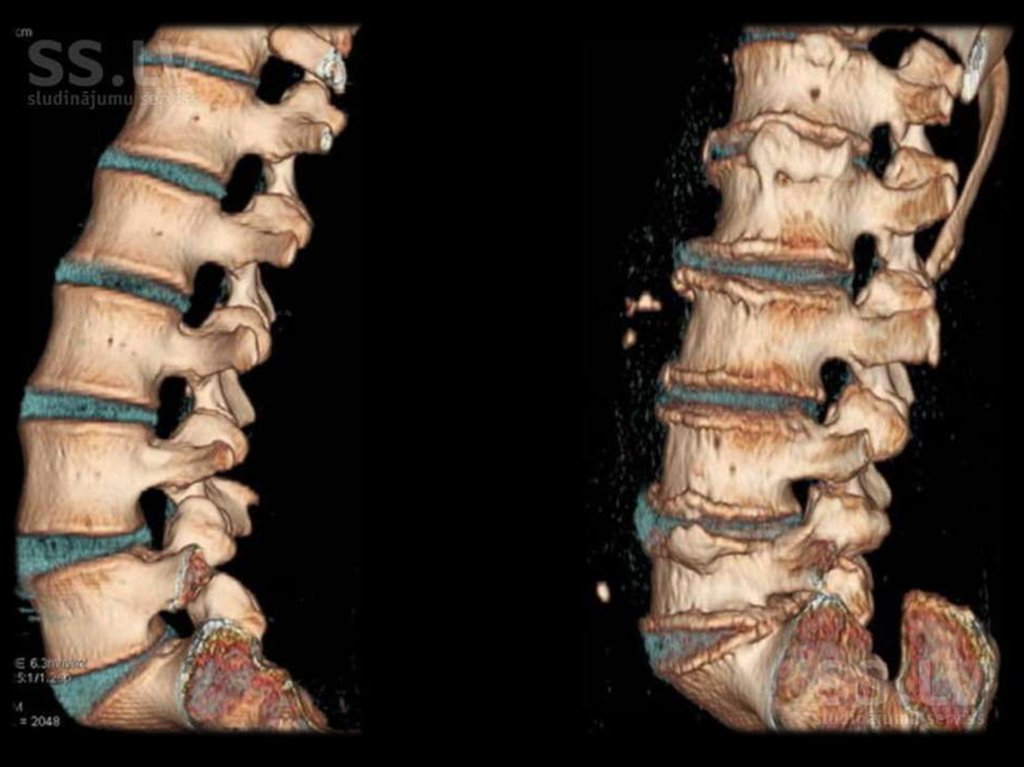

ДЕГЕНЕРАТИВНО-ДИСТРОФИЧЕЕСКИЕ ИЗМЕНЕНИЯ

ПОЗВОНОЧНИКА (СХЕМА)

1 – Остеофиты

2 – Грыжи Шморля

3 – Обызвествление диска

4 – Передние остеофиты

5 – Субхондральный склероз

6 – Сужение межпозвонковой щели

7 – Задний остеофит

8 – Клиновидная деформация

позвонка

9 – Сужение межпозвонкового

отверстия